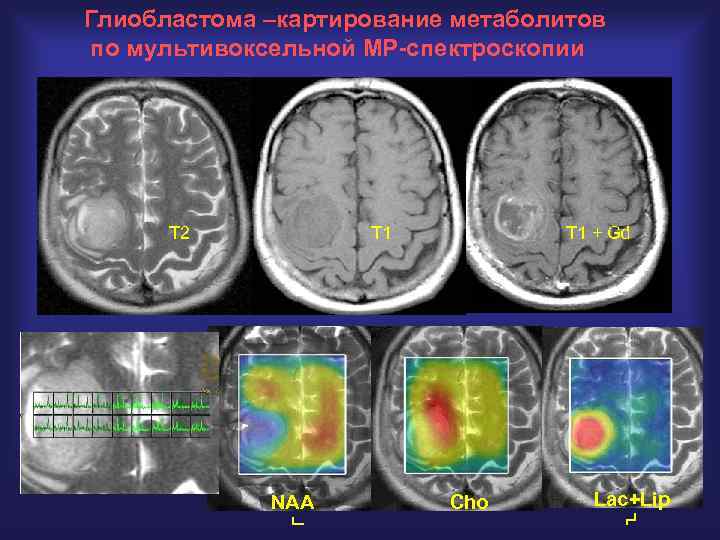

Глиобластома –картирование метаболитов по мультивоксельной МР-спектроскопии T 2 T 1 NAA T 1 + Gd Cho Lac+Lip